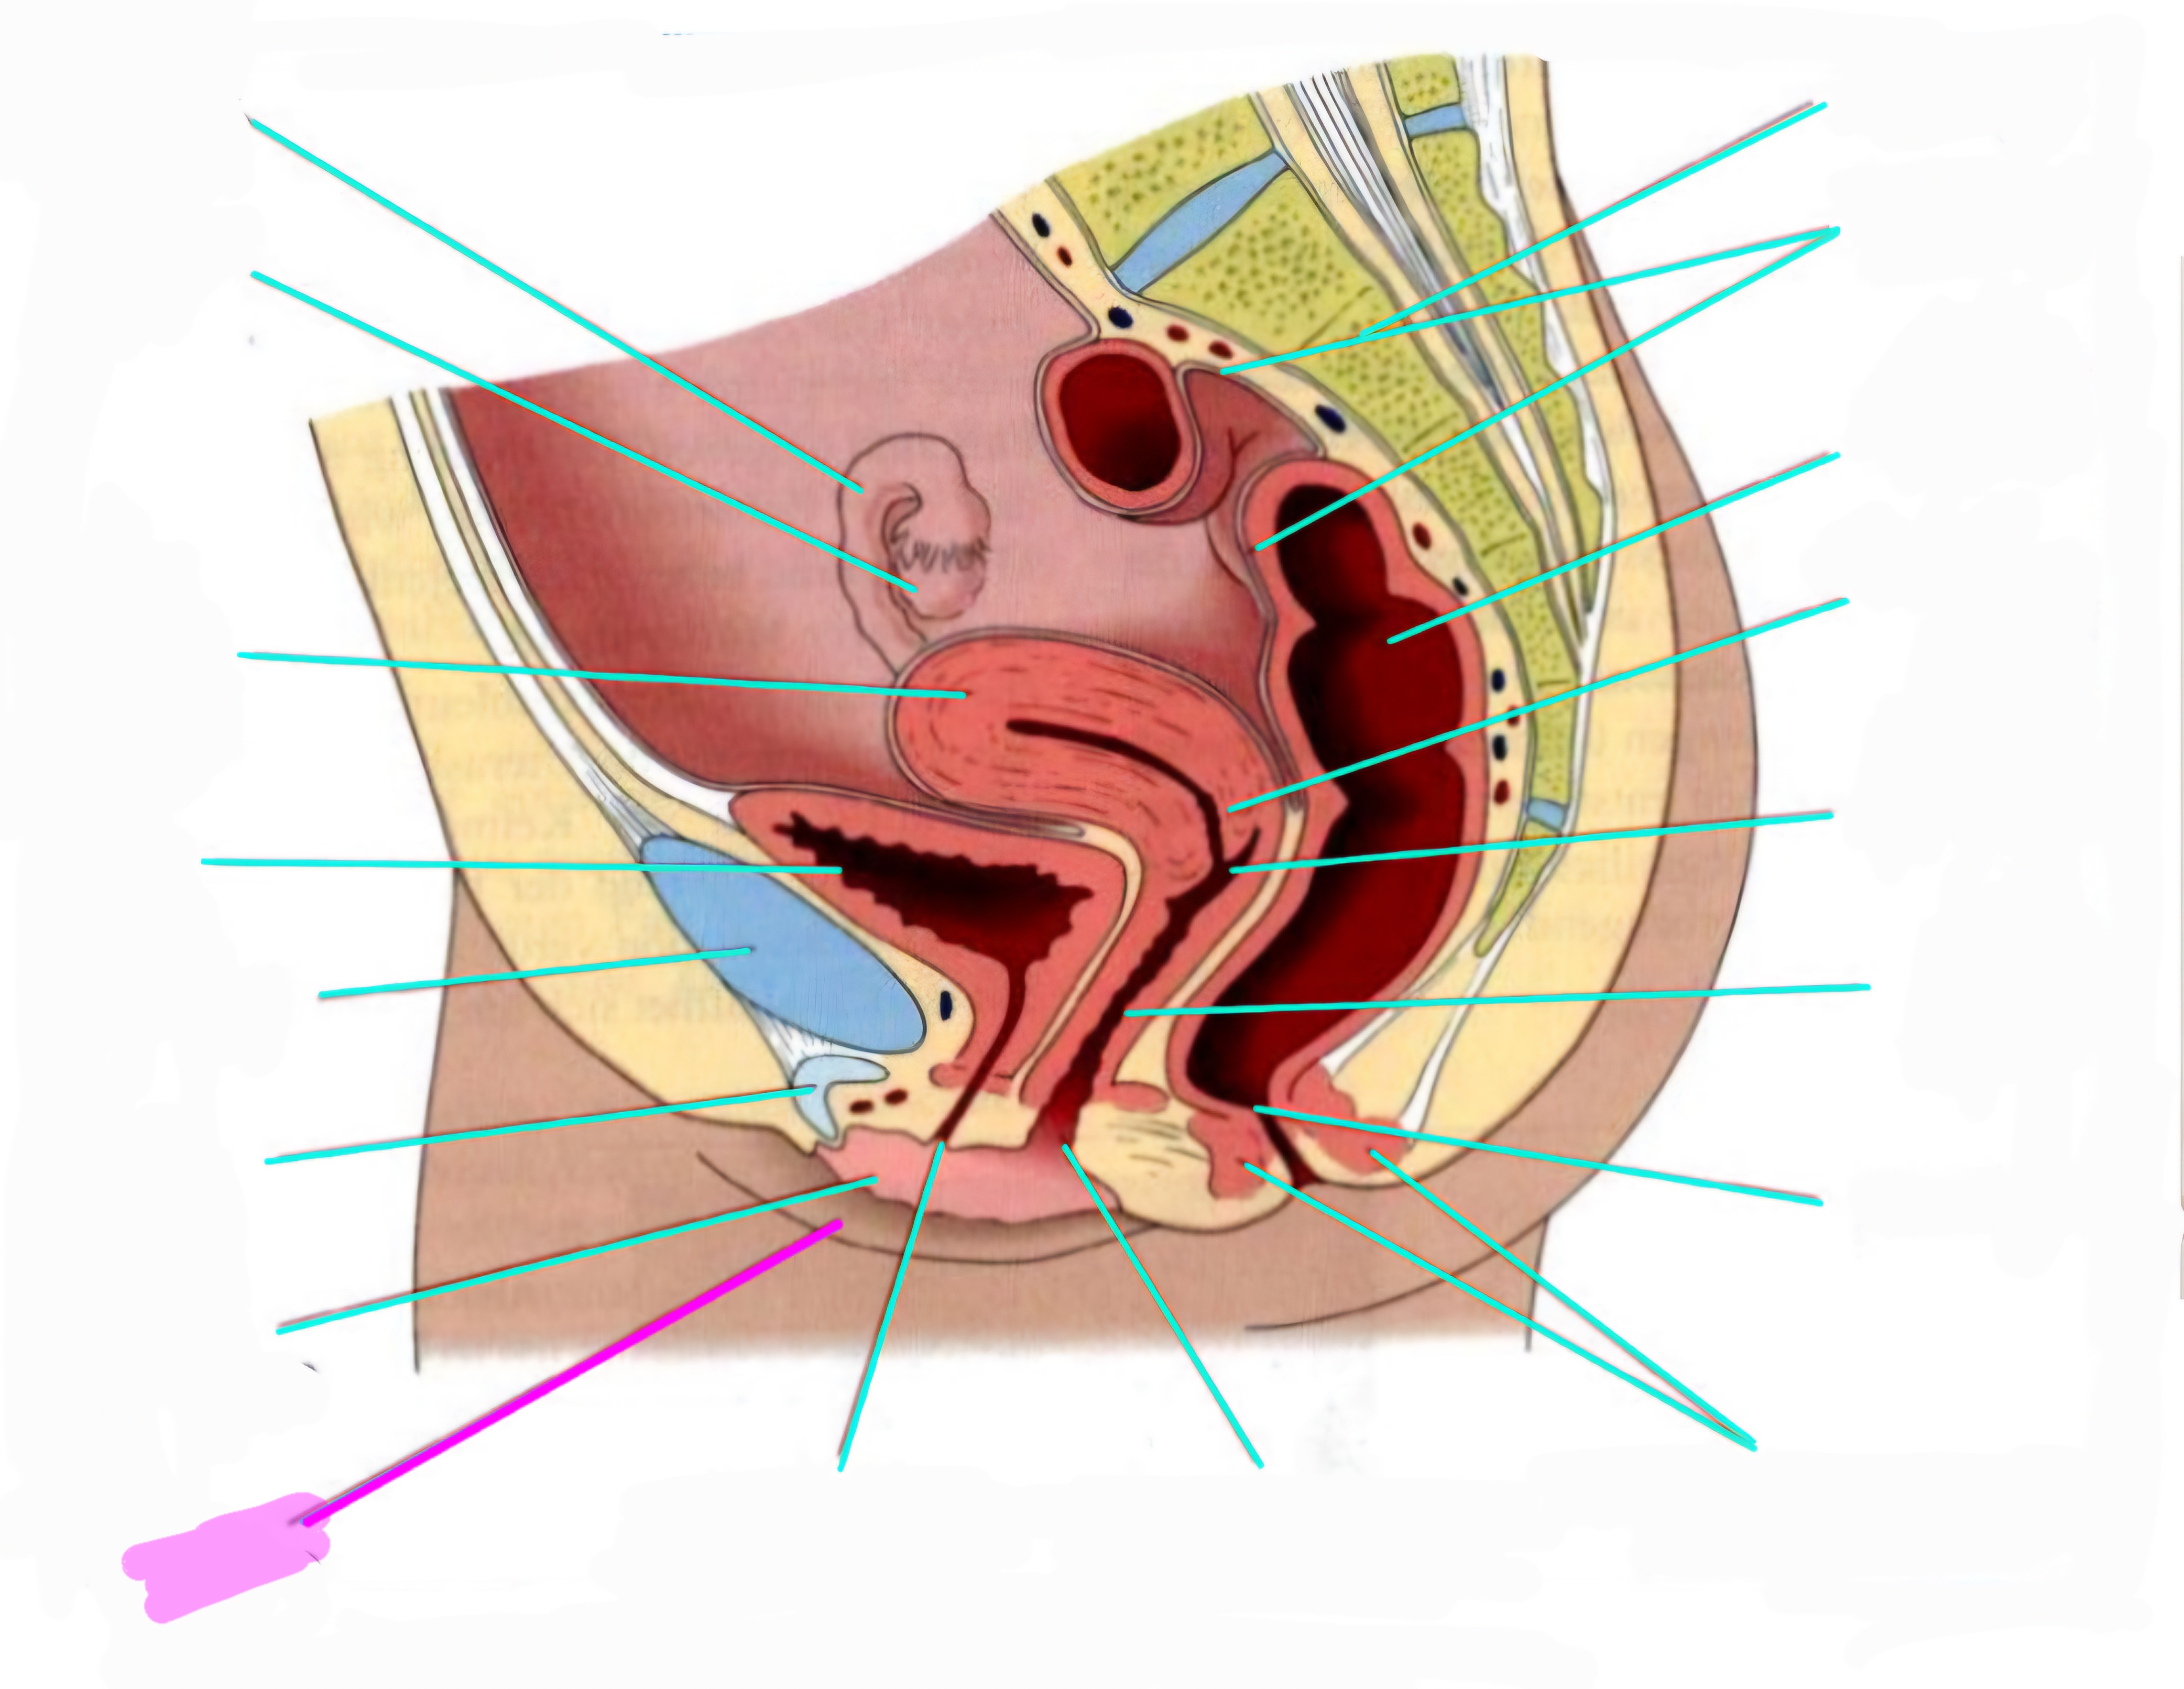

wbl. genital Anatomie

19 Terms

Tubea uterina (Eileiter)

Ovar (Eierstock)

Uterus (Gebärmutter)

Vesica Urinaria (Harnblase)

Symphyse

Klitoris

Labia minor pudendi (kleine schamlippen)

Labia Majoran pudendi (große Schamlippe)

Urethra (Harnröhre)

Introitus vaginae (Scheideneingang)

Sphincter ani externes (äußere Afterschließmuskel)

Anus (After)

Vagina (Scheide)

Portio (äußerer Muttermund)

Rektum (Mastdarm)

Zervix (Gebärmutterhals)

Peritoneum (Bauchfell)

Os sacrum (Kreuzbein)

Uterus: Topographie und Aufbau - wie groß ist er und wo liegt er?

7-8cm lang, Form einer umgedrehten Birne

Lage: im kleinen Becken zwischen Blase und Rektum

Antiversio: nach vorne geneigt, steht im Winkel zur Scheide

Antiflexio: in sich selbst geknickt, nach vorne abgebogen öber die Blase